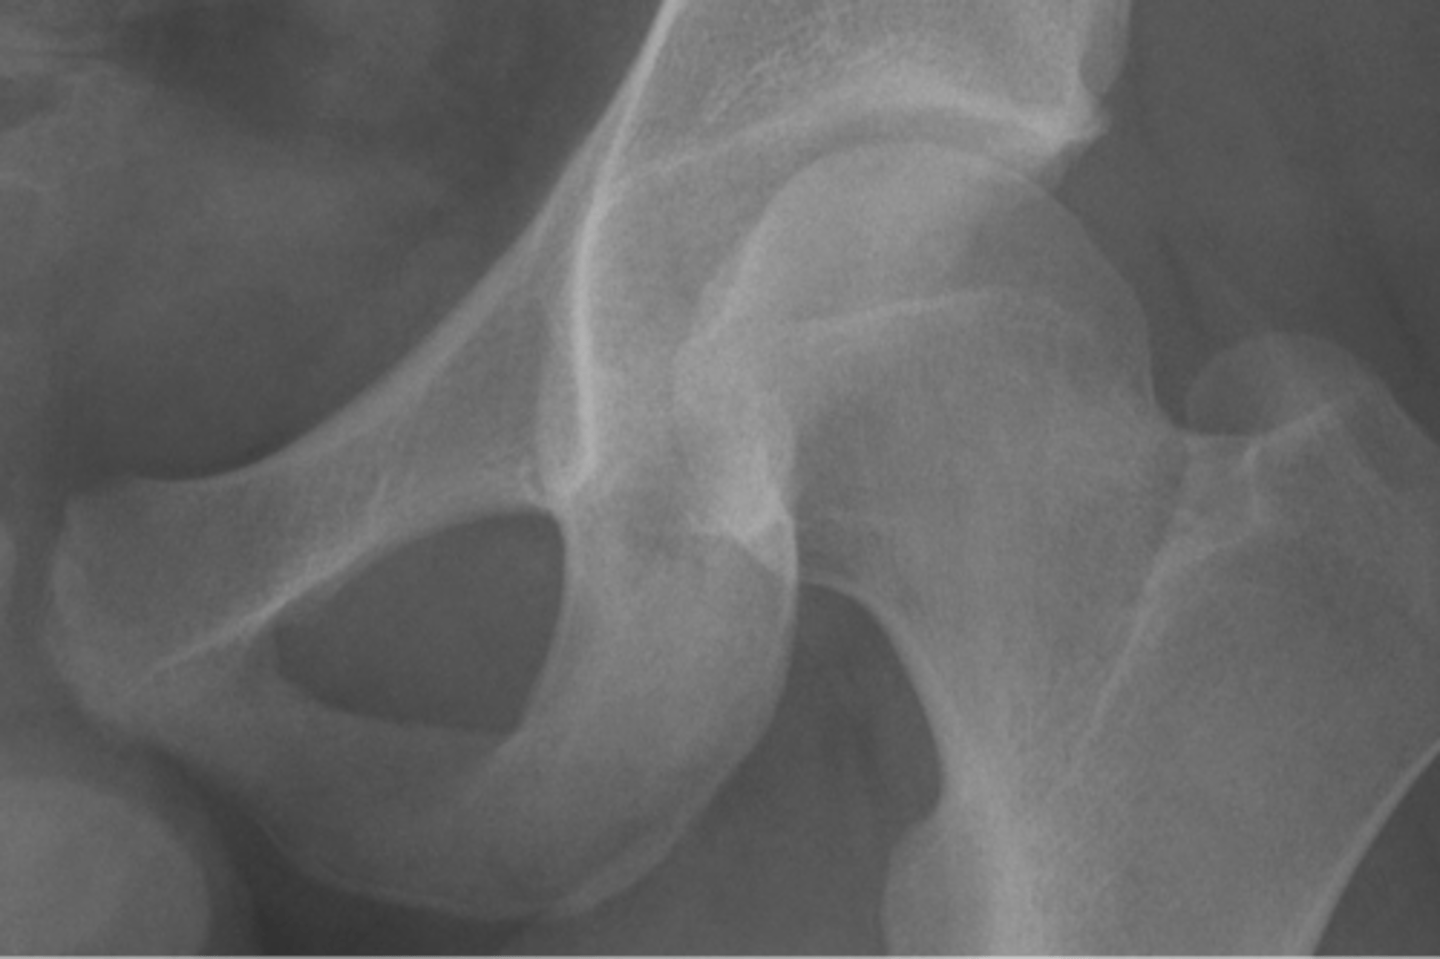

Kohler's teardrop distance

ID measurement line

<p>ID measurement line</p>

- AP pelvis

- AP hip

What views are needed to see Kohler's teardrop distance?

<p>What views are needed to see Kohler's teardrop distance?</p>

- Medial margin of femoral head

- Lateral border of teardrop

Kohler's teardrop distance landmarks

<p>Kohler's teardrop distance landmarks</p>

6-11 mm

Normal Kohler's teardrop distance measurement

<p>Normal Kohler's teardrop distance measurement</p>

39

2 mm

The normal Kohler's teardrop distance is 6-11 mm, and there should be no greater than a _____ difference when comparing to the contralateral side

<p>The normal Kohler's teardrop distance is 6-11 mm, and there should be no greater than a _____ difference when comparing to the contralateral side</p>

Hip joint effusion

Clinical significance of an enlarged Kohler's teardrop distance

<p>Clinical significance of an enlarged Kohler's teardrop distance</p>

Intracapsular swelling/joint effusion

Waldenstrom's sign is usually an indication of _____

<p>Waldenstrom's sign is usually an indication of _____</p>

Inflammatory arthritis

Clinical significance of a small Kohler's teardrop distance

<p>Clinical significance of a small Kohler's teardrop distance</p>